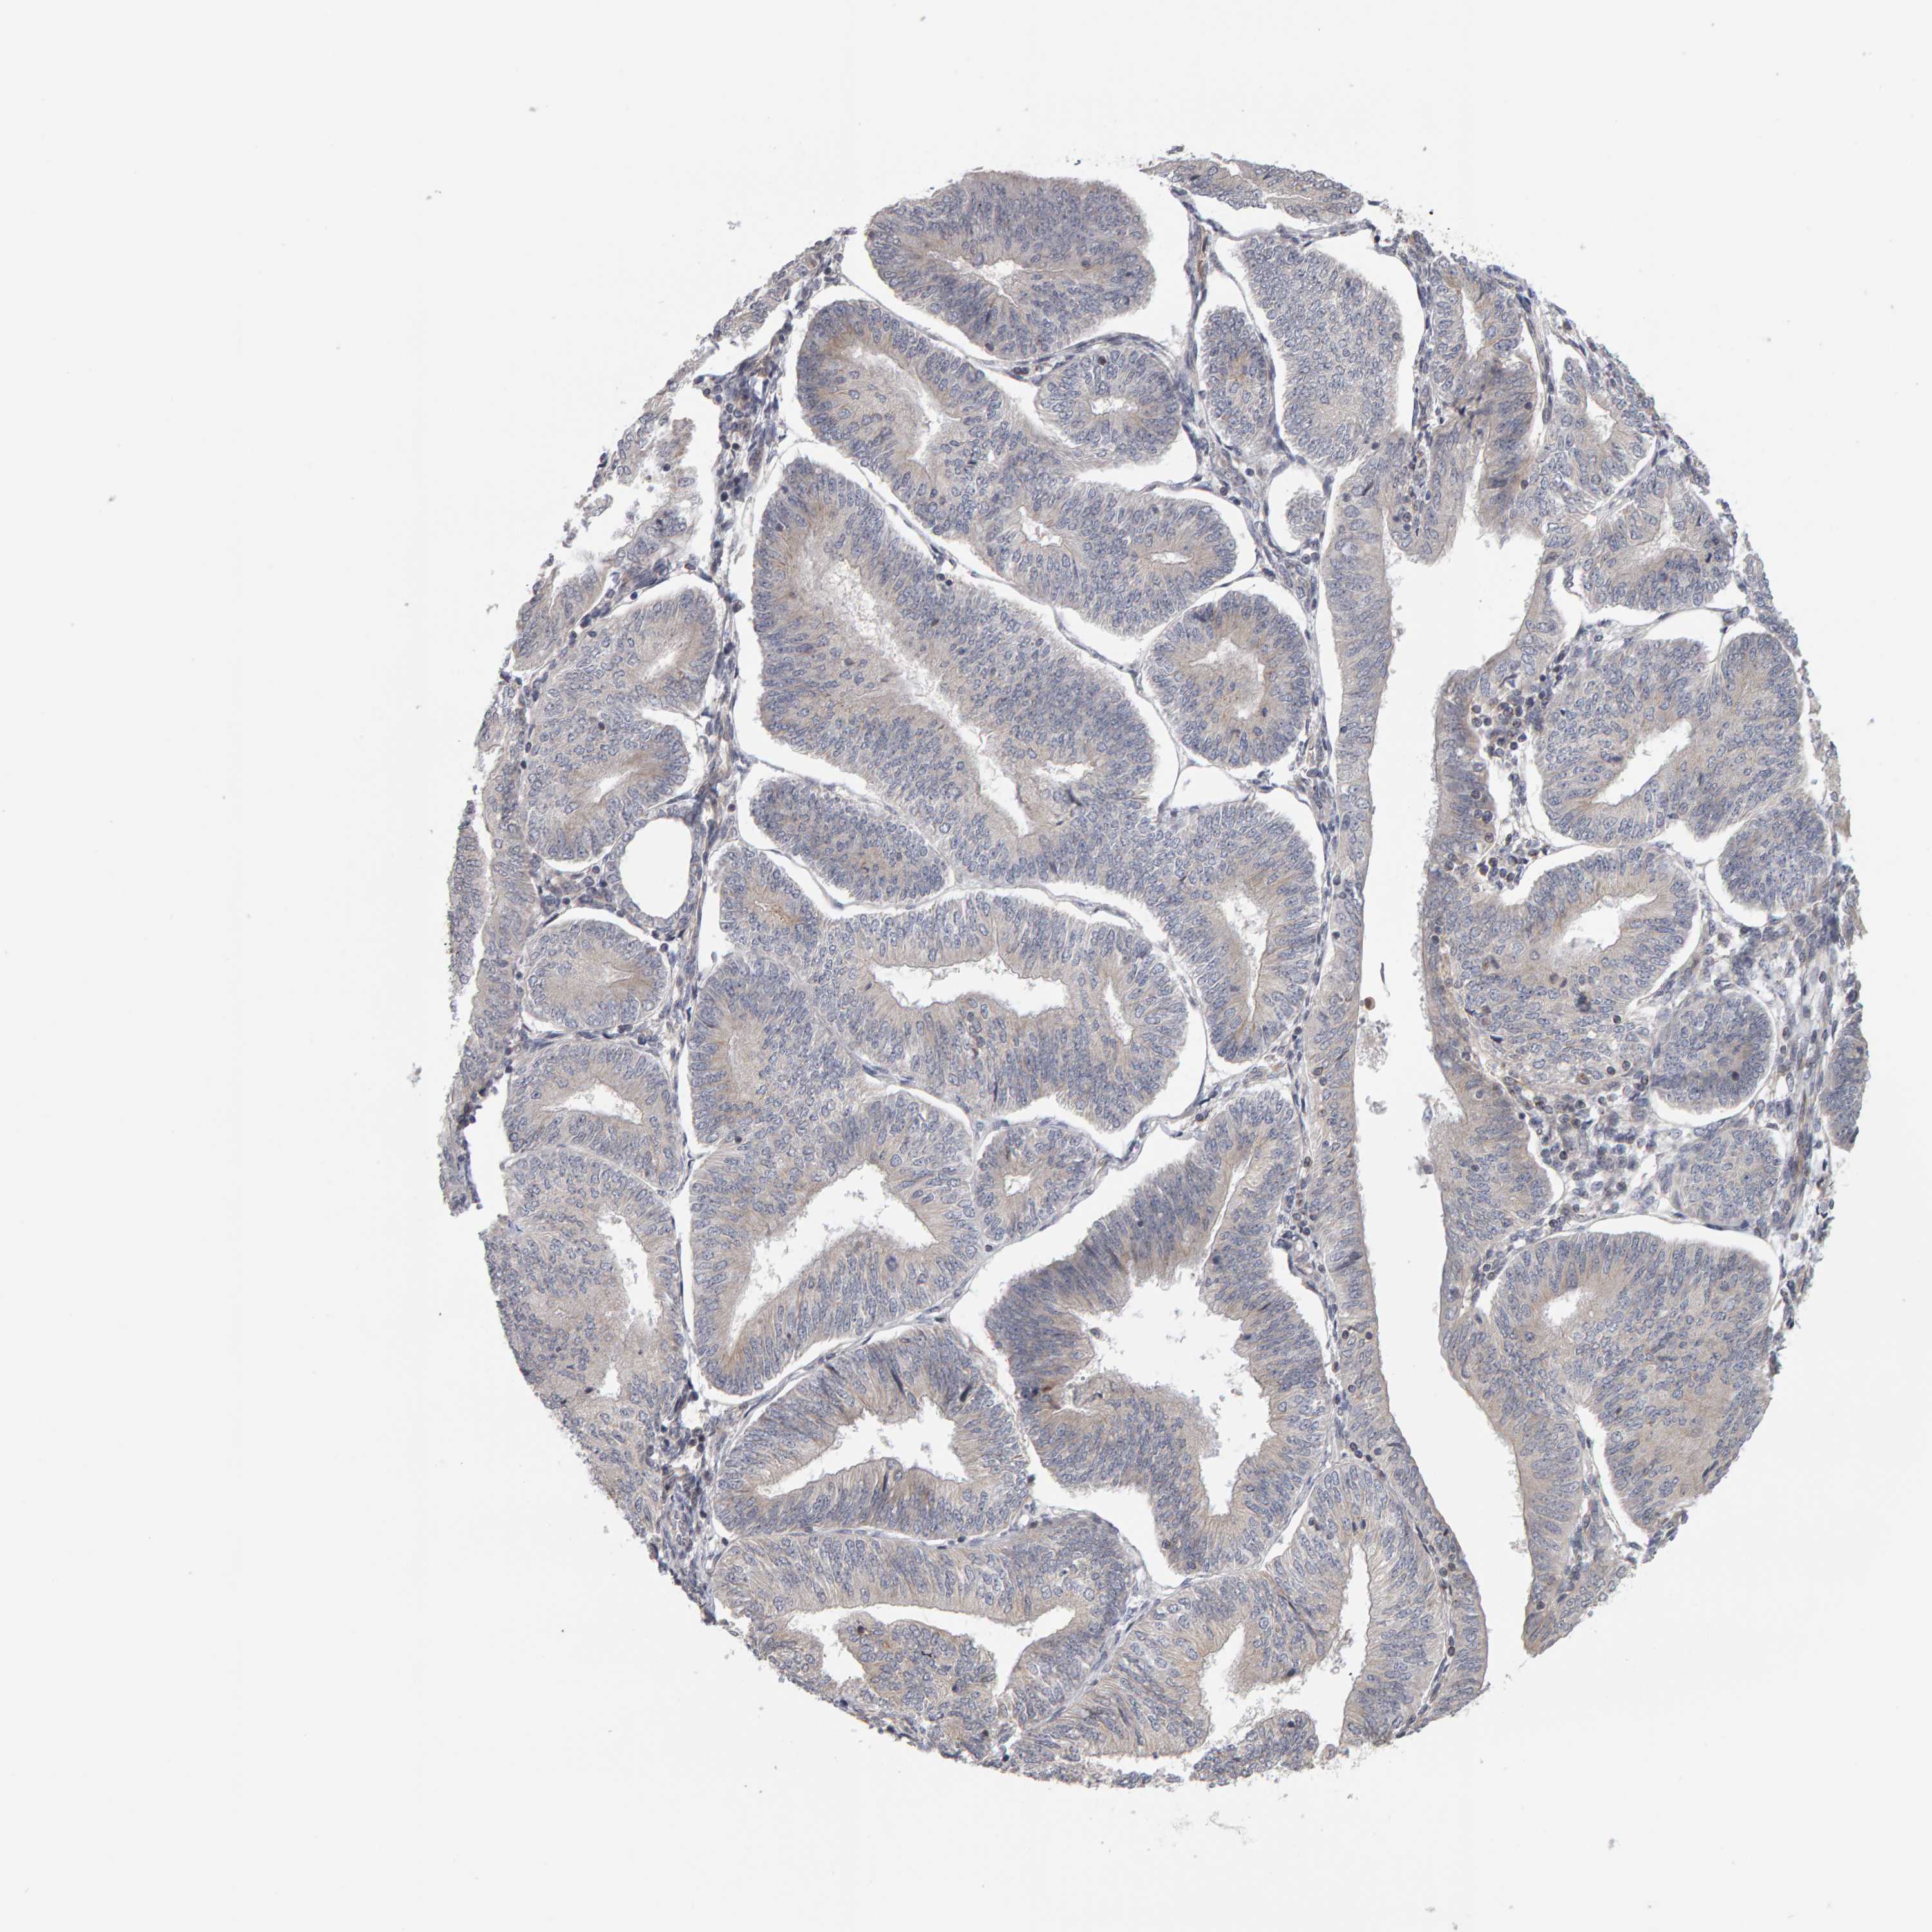

ENDOMETRIAL CANCER - Protein expressioni

A mouse-over function shows sample information and annotation data. Click on an image to view it in a full screen mode. Samples can be filtered based on level of antibody staining by selecting one or several of the following categories: high, medium, low and not detected. The assay and annotation is described here.

Note that samples used for immunohistochemistry by the Human Protein Atlas do not correspond to samples in the TCGA dataset.

Antibody stainingi

Antibody staining in the annotated cell types in the current human tissue is reported as not detected, low, medium, or high, based on conventional immunohistochemistry profiling in selected tissues. This score is based on the combination of the staining intensity and fraction of stained cells.

Each image is clickable and will lead to virtual microscopy that enables deeper exploration of all samples and also displays staining intensity scores, fraction scores and subcellular localization as well as patient and tissue information for each sample.

Antibody HPA023804

Antibody HPA075766

Staining

High

Medium

Low

Not detected

Intensity

Strong

Moderate

Weak

Negative

Quantity

>75%

75%-25%

<25%

None

Location

Nuclear

Cytoplasmic/membranous

Cytoplasmic/membranous,nuclear

Adenocarcinoma, NOS

Adenoma, NOS